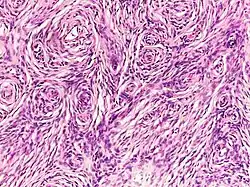

Neurofibroma

| Neurofibroma of the skin in a person with neurofibromatosis type I | |

A neurofibroma is a benign nerve-sheath tumor in the peripheral nervous system. In 90% of cases, they are found as stand-alone tumors (solitary neurofibroma, solitary nerve sheath tumor[1] or sporadic neurofibroma[1]), while the remainder are found in persons with neurofibromatosis type I (NF1), an autosomal-dominant genetically inherited disease. They can result in a range of symptoms from physical disfiguration and pain to cognitive disability.